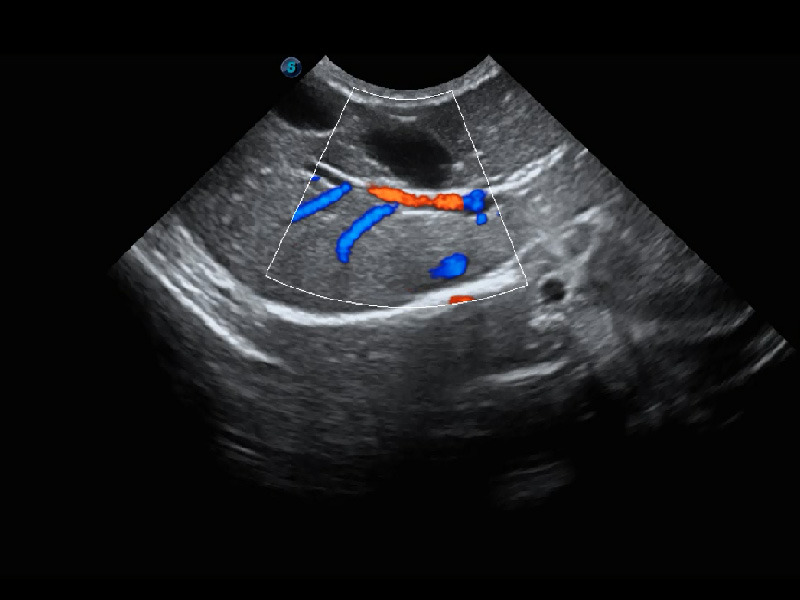

ProPet 60 作为一款高端台式动物超声设备,为动物医生的日常诊断提供了一系列贴合动物临床需求、解决临床实际问题的高级成像功能。凭借全系列高清探头,满足医生对腹部、心脏、生殖、浅表、肌骨等成像的所有需求,切实帮助您提升检查效率,提高诊断信心。

兽用彩色多普勒超声诊断系统

动物是人类最亲密的朋友和最值得信赖的伙伴。银河集团官网也一直致力于探索动物专用的超声影像解决方案。 全新推出的ProPet系列,是银河集团官网在动物超声影像智能化、专业化、精准化的一次跨越式革新。动物不能用言语来表述自己的不适,通过超声影像,ProPet系列搭建了动物医生与不同物种沟通的“桥梁”,为动物医生注入了“治愈之力”。